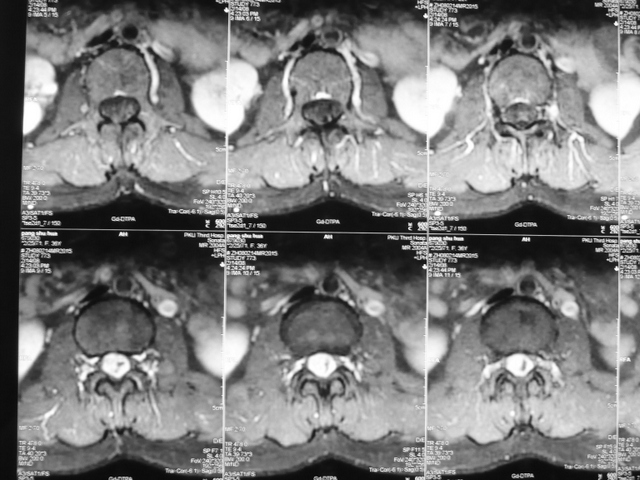

腰椎管内神经鞘瘤

P1030144.JPGP1030138.JPG